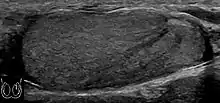

Seminoma is the most common tumor type in cryptorchid testes. The risk of developing a seminoma is increased in patients with cryptorchidism, even after orchiopexy. There is an increased incidence of malignancy developing in the contralateral testis too, hence sonography is sometimes used to screen for an occult tumor in the remaining testis. On US images, seminomas are generally uniformly hypoechoic, larger tumors may be more heterogeneous [Fig. 3]. Seminomas are usually confined by the tunica albuginea and rarely extend to peritesticular structures. Lymphatic spread to retroperitoneal lymph nodes and hematogenous metastases to lung, brain, or both are evident in about 25% of patients at the time of presentation.